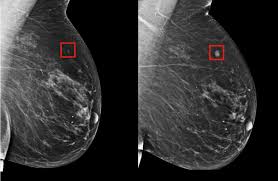

How Cancers Grow Cancer Research Uk from www.cancerresearchuk.org Breast cancers in young women tend to grow more rapidly than breast cancers in older women and have a higher tumor grade menopausal state: Cancer can develop anywhere in the body. Instead, the cancer cells build up in the blood and sometimes the bone marrow. When removed, benign tumors usually don't grow back, whereas cancerous tumors sometimes do. Barrett's esophagus occurs in only a small proportion of all those with gerd. Stages help doctors decide which treatments are most likely to work and give a general outlook. What is a stem cell? That can slow the growth of the tumor.

Cell Division Cancer Learn Science At Scitable from www.nature.com One indication of the multistep development of cancer is that most cancers develop late in life. Doctors call this superficial cancer growth or carcinoma in situ (cis). Typically, cancer signs and symptoms first appear when the cancerous tumor or mass has grown large enough that it begins to push against nearby organs and tissue, blood vessels, and nerves. In addition, occupational exposures, such as asbestos or radon. Different cell compartments are involved in the mechanism of chemoresistance, and multiple mechanisms can be activated by single cells at different times of the cancer. Certain inherited dna mutations (changes) can dramatically increase the risk for developing certain cancers and are linked to many of the cancers that run in some families. For example, the lining of the bladder or the breast ducts. Cancer is the name for a group of more than 100 diseases in which cells begin to grow out of control.